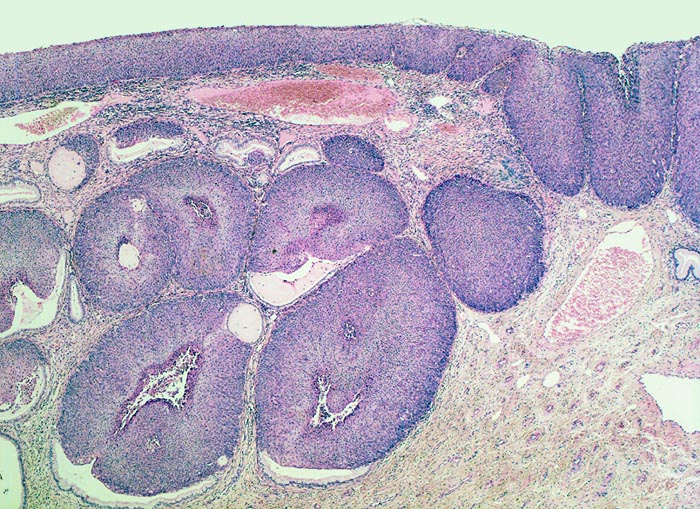

Carcinoma in situ (CIN III) des Plattenepithels

Das metaplastische Plattenepithel der Portio ist verdickt und erscheint aufgrund der erhöhten Zelldichte und der vergrösserten Kerne basophil. Eine Ausreifung der Zellen zur Oberfläche hin ist nicht erkennbar (=Cis). Das Carcinoma in situ wächst in vorbestehende endozervikale Drüsenschläuche ein.

Die Umwandlungszone liegt dort, wo das metaplastische Plattenepithel die zervikalen Drüsen überwächst. An dieser Stelle finden sich besonders oft dysplastische Veränderungen des Portioepithels. Das Vorwachsen des dysplastischen Epithels in die endozervikalen Drüsenschläuche ist nicht mit Invasion gleichzusetzen, da das dysplastische Plattenepithel die Basalmembran der Drüsen nicht durchbricht (daran erkennbar, dass das vorwachsende Epithel scharf begrenzt ist und keine desmoplastische Stromabildung induziert).